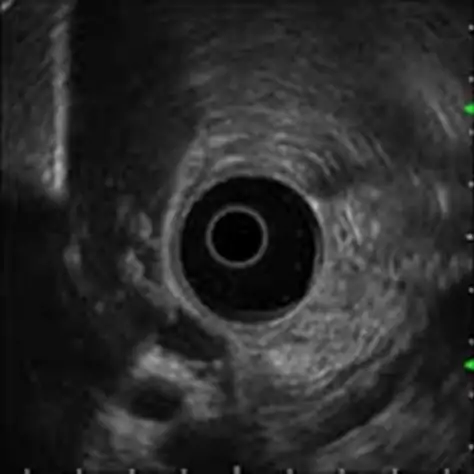

EUS(超音波内視鏡検査)

超音波検査装置のついた内視鏡を用いて、消化管さらに胆のう、膵臓などの腫瘍などを詳しく調べるものです。超音波内視鏡検査は専門的な検査であり、鎮静剤を用いて行います。